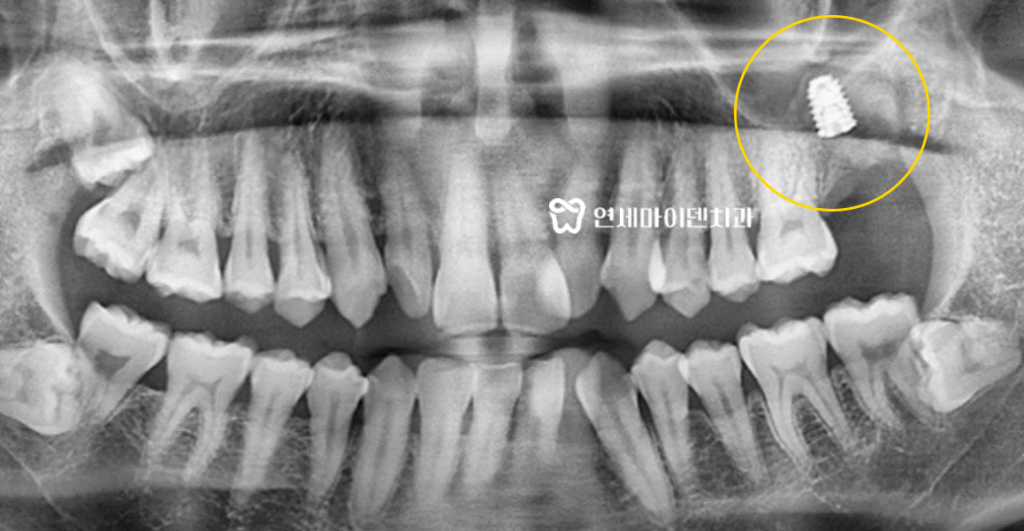

엑스레이 상으로 확인해보니

어금니 바로 아래에 매복 사랑니가 있는 것이 보입니다.보통 사랑니는 잇몸 끝쪽에 있지만

이 환자분의 사랑니는 어금니 바로 아래에서 염증을 유발하고 있었습니다.

특히 엑스레이상 까맣게 보이는 염증으로

잇몸 뼈가 이미 많이 녹아있는 상태였습니다.고난이도 치료를 많이 시행하고 있는 저희 연세마이덴치과지만

CT 촬영 후 3D 네비게이션을 통해 3차원적으로

임플란트를 식립할 최적의 위치와 크기, 깊이를 설정해주었습니다.정밀하게 식립 위치를 계산하고 최적의 깊이까지 임플란트를 넣어주는 것이